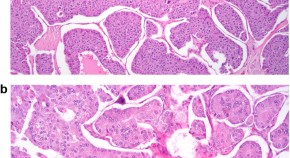

Identification and classification of dysplasia in patients with ulcerative colitis or Crohn's disease in the large intestine is a challenge. Surveillance programs in these patients aim to detect colitis-associated dysplasia at an early stage, as the risk of these patients developing colorectal cancer is considerable. Good communication and discussion between pathologists and endoscopists is essential to help reach unequivocal diagnoses and to improve the management of colitis-associated dysplasia.